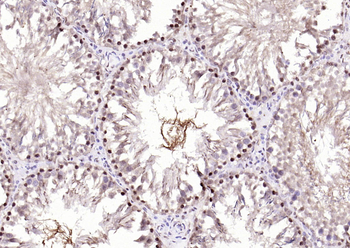

50 μl, 100 μl - MARK3 Recombinant Rabbit Monoclonal Antibody [orb704310]Featured

ICC, IF, IHC-Fr, IHC-P

Human, Mouse

Rat

Rabbit

Recombinant

Unconjugated

50 μl, 100 μl - Featured